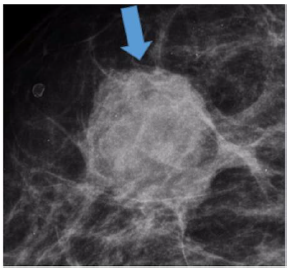

A imagem obtida em corte ampliado de mamografia pode ser classificada pelo Breast Imaging Reporting and Data System como: